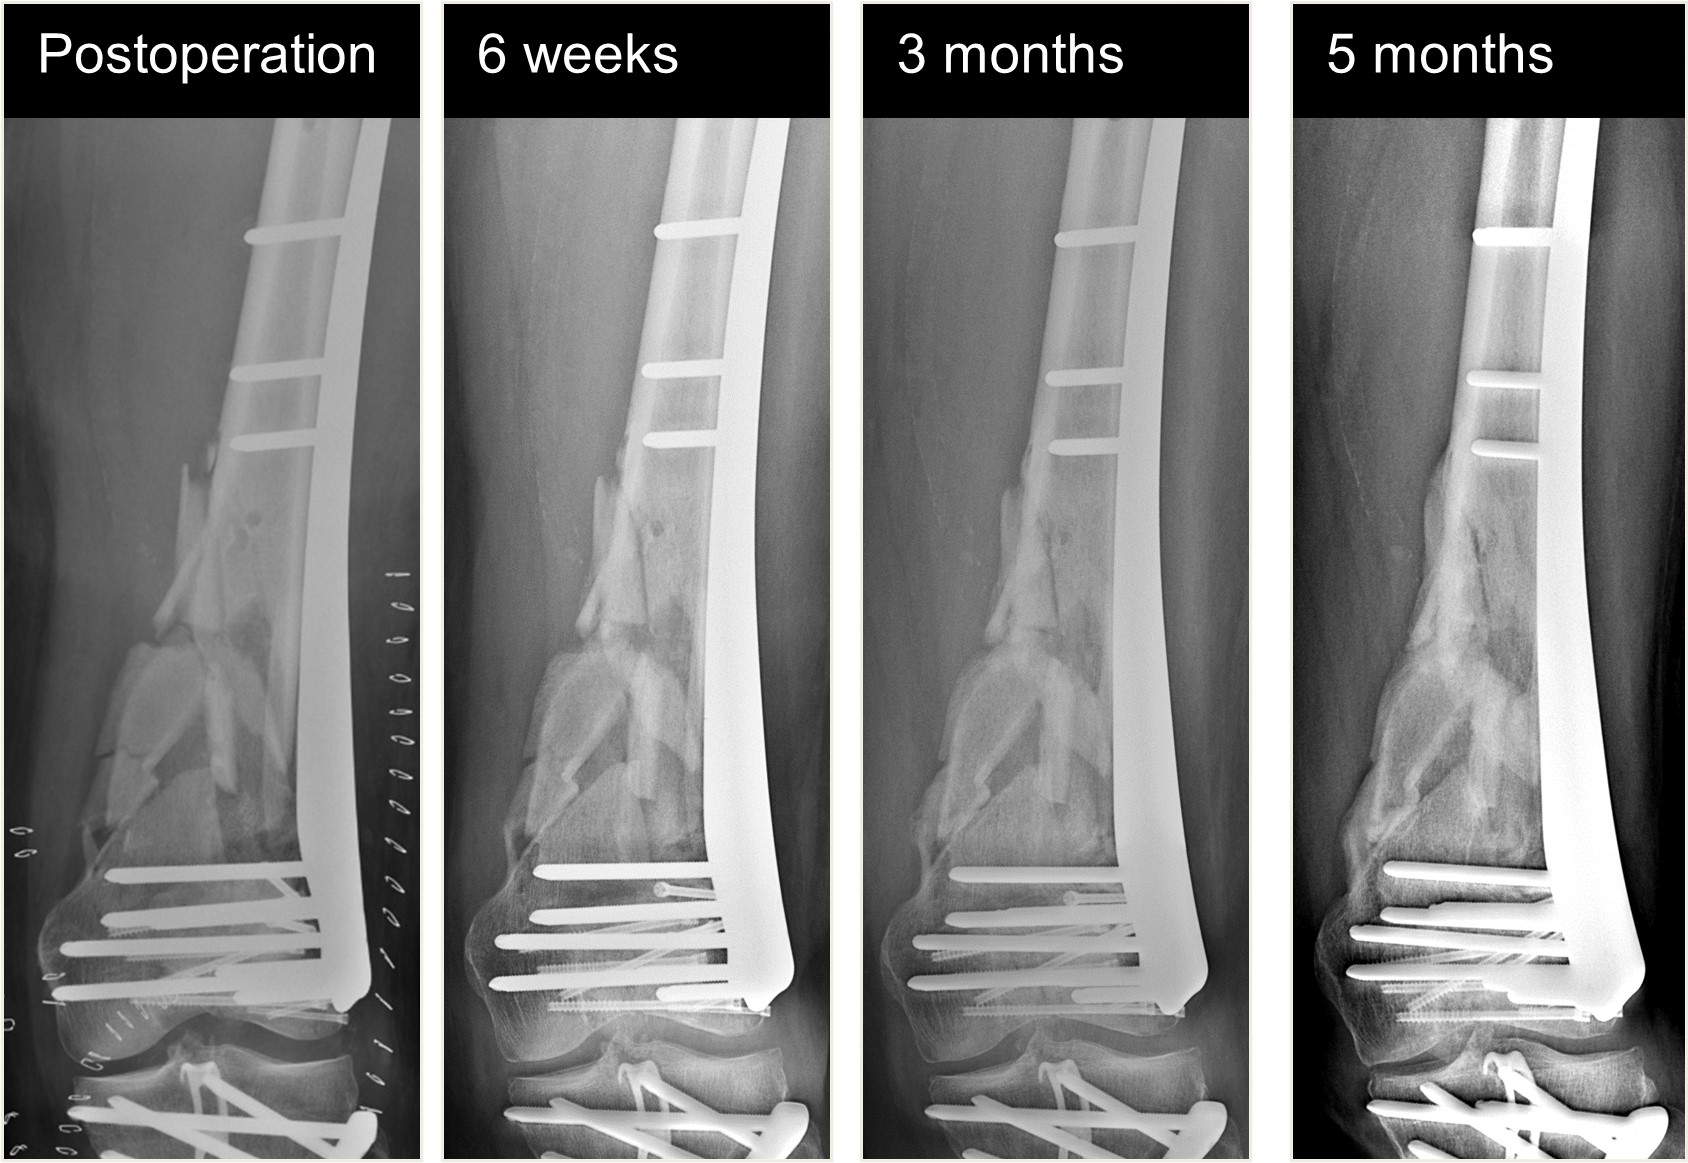

An 82-year-old man fell while climbing and sustained a periprosthetic distal femoral fracture (Fig 8). The fracture was reduced and then fixed with a Biphasic Plate DF (Fig 9). The patient was allowed immediate full weight bearing and presented with a decent amount of callus at the fracture site after 6 weeks (Fig 10).

The patient showed uneventful healing and returned to preoperative function 2.5 months postoperation. Figure 11 shows the callus formation 3 months postoperation.